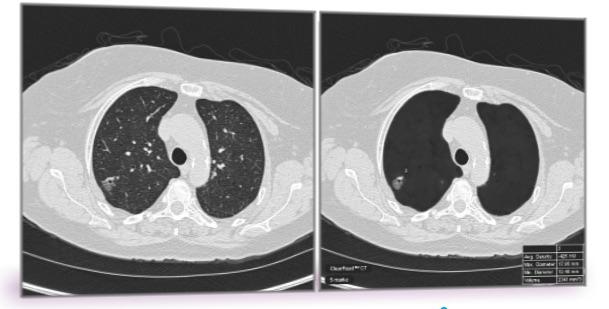

CT exams are routinely used for tumor staging and monitoring treatment response. Using a field of study called radiomics, researchers can extract quantitative, or measurable, data from CT images that can reveal disease characteristics not visible in the images alone.

A computer analyzed the CT images of lung cancer to identify unique patterns of heterogeneity both inside and outside the tumor. These patterns were then compared between CT scans of patients who did and did not respond to chemotherapy. These feature patterns were then used to train a machine learning classifier to identify the likelihood that a lung cancer patient would respond to chemotherapy.

The results showed that the radiomic features derived from within the tumor and the area around the tumor were able to distinguish patients who responded to chemotherapy from those who did not. In addition, the radiomic features predicted time to progression and overall survival.

“Despite the large number of studies in the CT-radiomics space, the immediate surrounding tumor area, or the peritumoral region, has remained relatively unexplored,” Khorrami said. “Our results showed clear evidence of the role of peritumoral texture patterns in predicting response and time to progression after chemotherapy.”